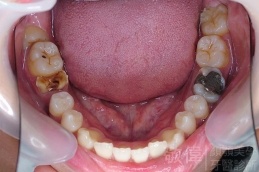

變臉矯正,原來戽斗妹跟大歪臉變成自信正妹

經由本院3D數影X光影像儀分析、與3D齒顎顏矯正技術,再配合口腔顎面正顎專科醫師施以正顎手術治療,雙方共同合作,使患者臉部外觀有很好的改善,大歪變小歪,產生了天南地北的大改變,她的人生也整個變得不一樣。

因為矯正與正顎手術的配合,使「戽斗妹」變成了「陽光正妹」,完全的改變了她的人生,在面對各種場合、與人交際都散發出自信微笑。所以,奉勸家長,如果小朋友有臉顎畸型的問題,應該考慮配合做這種簡單、安全、有效的正顎手術。